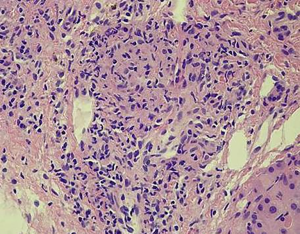

The third patient was a 55-year-old male who had been diagnosed with rectal adenocarcinoma and bilateral renal cell carcinoma 2 years ago. Preoperative abdominal CT examination revealed an ill-defined, low attenuating lesion in segment S5 of the liver (measuring <1 cm). The laboratory examinations showed no obvious evidence of infection signs such as increased CRP level or WBC counting. Therefore, the initial diagnosis was focal fat deposition, and metastasis is less likely. Since the lesion was very small, no interventional treatments were administered, and a close follow-up was suggested. He underwent rectectomy and bilateral nephrectomy and sustained on long-term hemodialysis after the operation. However, the follow-up CT and MRI examinations in the half a year after the surgery revealed that the previous nodule in segment S5 of the liver increased in size from 1 to 2 cm with peripheral enhancement after administration of contrast agent (Figure 3). The F-18 FDG PET-CT demonstrated a hypermetabolic nodule in S5 of the liver, which indicated a high suspicion of hepatic metastasis. Finally, the successful FNA was done on this nodule of the liver. Microscopically, the nodule exhibited a caseating granuloma with a mixture of epithelioid histiocytes, inflammatory cells and Langhans giant cells in the background of fibrous tissue (Figure 4). Moreover, further NTM and MTB PCR kit revealed positive for NTM and negative for MTB. The patient received antitubercular treatment and was responsive to therapy. The latest follow-up CT showed the nodule decreased slightly from 2 to 1.4 cm in size and no other newly appeared lesions in the liver (Figure 3D).